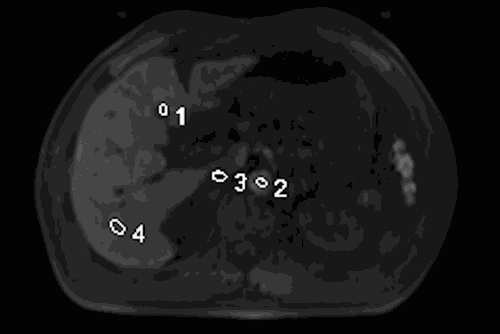

该设备可以实现更为先进的人工智能全自动化扫描。病人躺上扫描床后,无需激光灯定位,告知检查部位会自动感知病人解剖,精准地对其扫描部位进行定位。同时,扫描时可发现小到数毫米的肿瘤,对肿瘤的早期发现和治疗具有重要参考和辅助诊断价值。